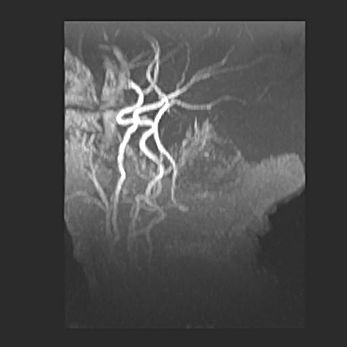

Множественные кисты обоих полушарий головного мозга, наибольшая из них в правой затылочной области. Ассиметричная атрофическая гидроцефалия.

Возраст: 7 месяцев

Вес: 5660 г

Пол: мужской

Окружность головы: 41,5 см

Срок гестации: 28-29 недель

Кисты головного мозга развиваются в результате многоочаговых некрозов вещества мозга и возникают вследствие перенесенной перинатальной инфекции, менингитов, энцефалитов, асфиксии, родовой травмы, расстройств мозгового кровообращения различного генеза. Образованию кист в веществе головного мозга плодов и новорожденных способствуют такие факторы, как высокое содержание в нем воды, недостаточная (или отсутствие) миелинизация и слабая астроглиальная реакция на повреждение.

Кисты могут сочетаться с гидроцефалией и другими поражениями головного мозга.